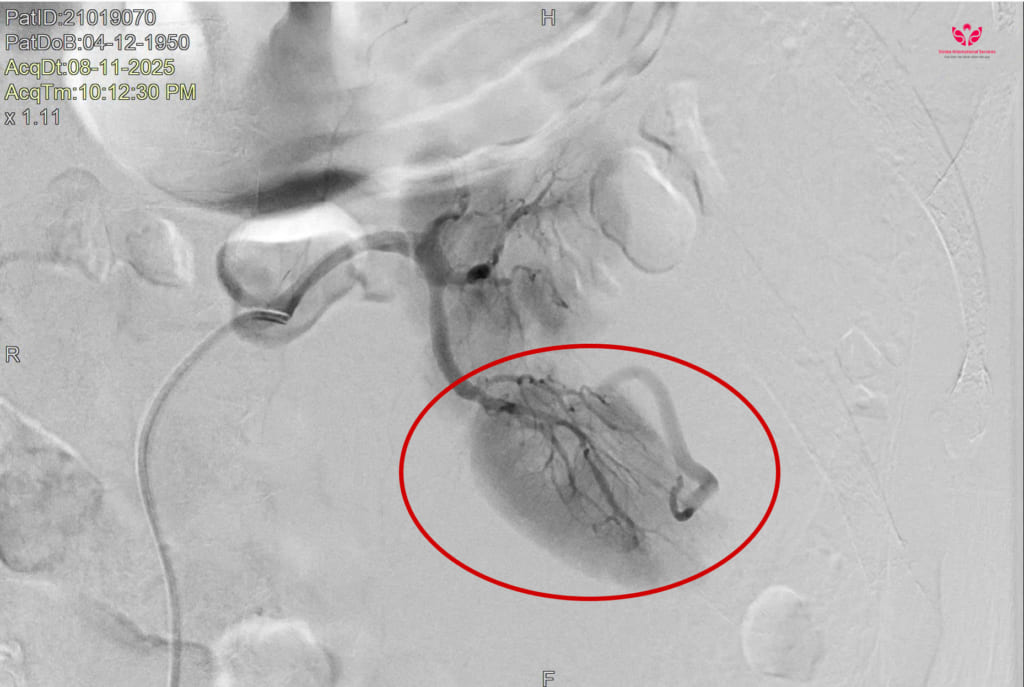

BS.CK2 Ngô Minh Tuấn – Trưởng đơn vị Can thiệp mạch máu tạng ngoại biên chia sẻ: Sau thời gian khoảng 30 phút, chúng tôi đã xác định chính xác vị trí vỡ thận có dấu thoát mạch tại phân thùy sau thận trái và chúng tôi đã tiến hành gây tắc 2 nhánh động mạch đang chảy máu bằng keo sinh học. Sau can thiệp bệnh nhân giảm đau bụng, tình trạng huyết động tạm ổn ngay tại bàn thực hiện thủ thuật.